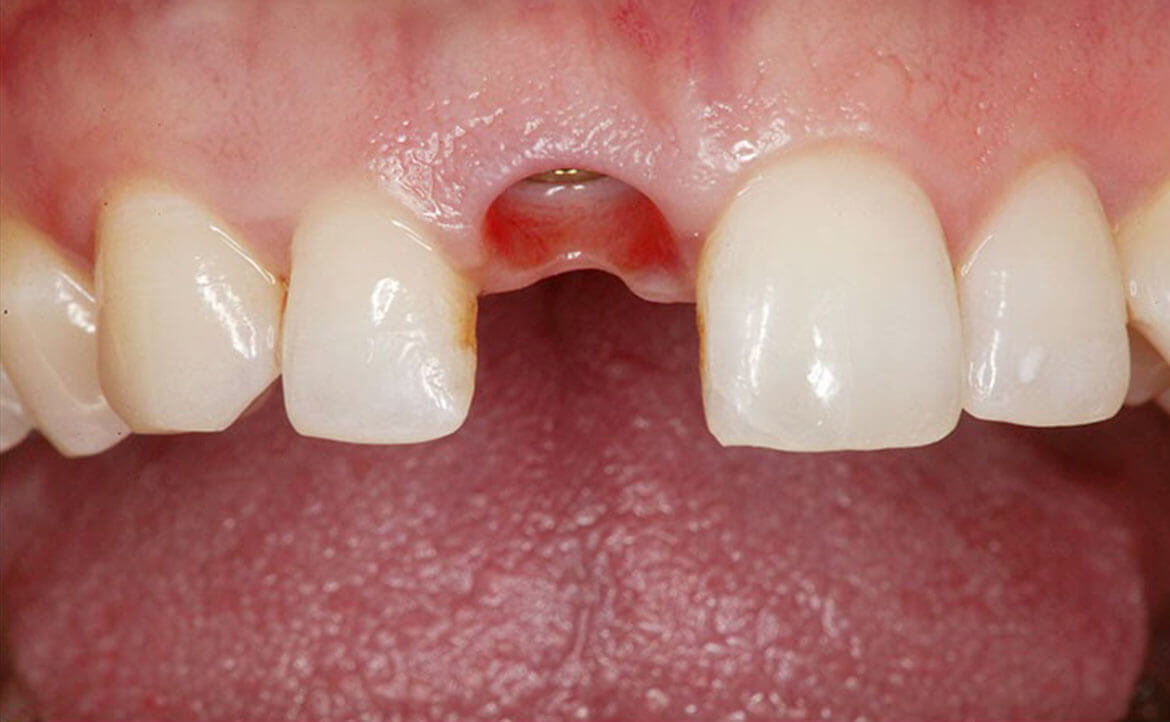

Implantul dentar este un dispozitiv confecționat din titan, care are rolul de a înlocui absența unuia sau mai multor dinți. Implantul îndeplinește funcția de radacină pentru viitoarea coroană dentară. Este fixat după intervențiile pregătitoare.